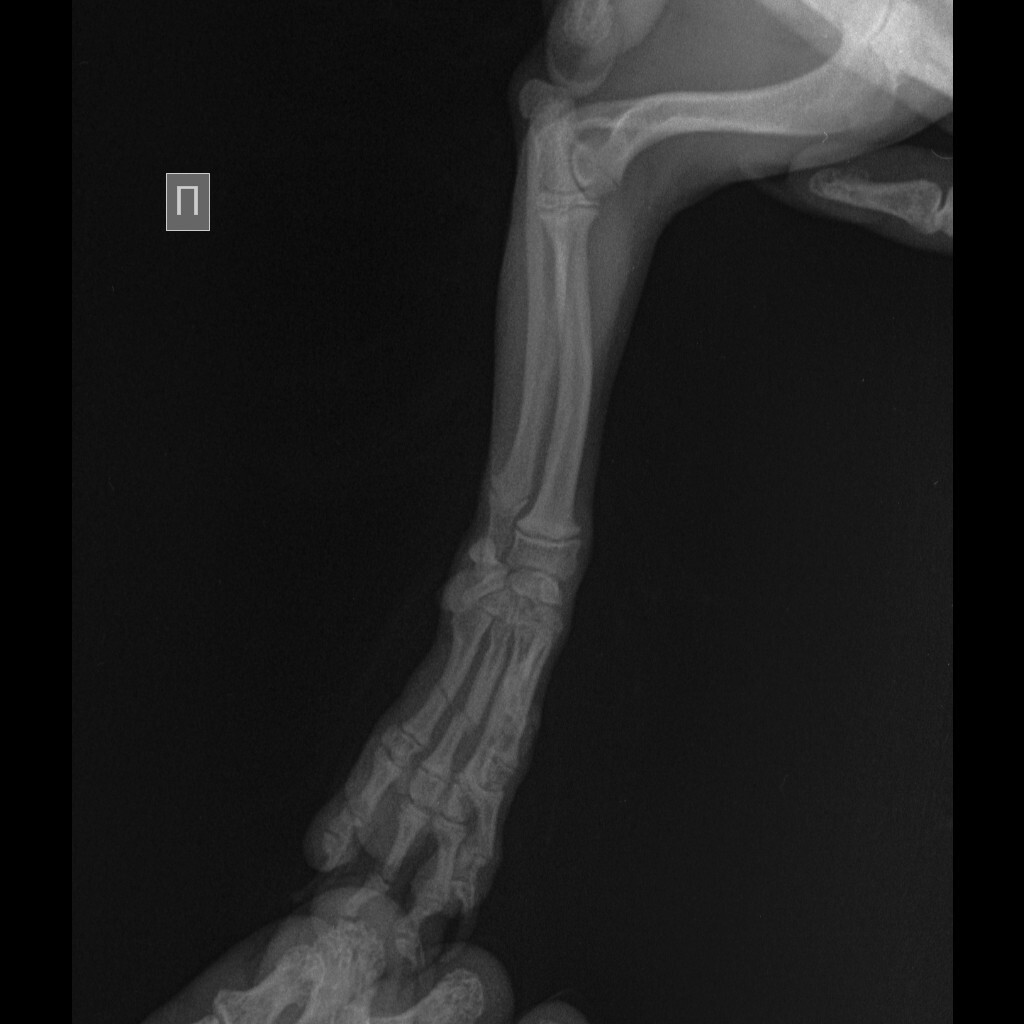

Вопрос вот в чем, щенок йоркширского терьера сломал 4 пальца на лапке. Ветеринарная клиника нашего небольшого города рекомендует делать операцию. Другой врач, в клинике побольше советует ничего не делать. Кому верить?

Вот на этом снимке хорошо виден перелом